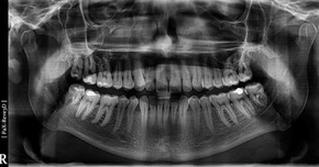

Określ rodzaj zamieszczonego zdjęcia rentgenowskiego.